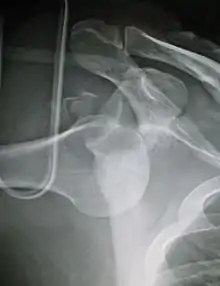

Anterior dislocation of the left shoulder. | |

A dislocated shoulder is when the head of the humerus is out of the shoulder joint.[2] Symptoms include shoulder pain and instability.[2] Complications may include a Bankart lesion, Hill-Sachs lesion, rotator cuff tear, or injury to the axillary nerve.[1]

A shoulder dislocation often occurs as a result of a fall onto an outstretched arm or onto the shoulder.[3] Diagnosis is typically based on symptoms and confirmed by X-rays.[2] They are classified as anterior, posterior, inferior, and superior with most being anterior.[2][1]

In over 95% of shoulder dislocations, the humerus is displaced anteriorly.[6] In most of those, the head of the humerus comes to rest under the coracoid process, referred to as sub-coracoid dislocation. Sub-glenoid, subclavicular, and, very rarely, intrathoracic or retroperitoneal dislocations may also occur.[7]

Anterior dislocations are usually caused by a direct blow to, or fall on, an outstretched arm. The person typically holds his/her arm externally rotated and slightly abducted.